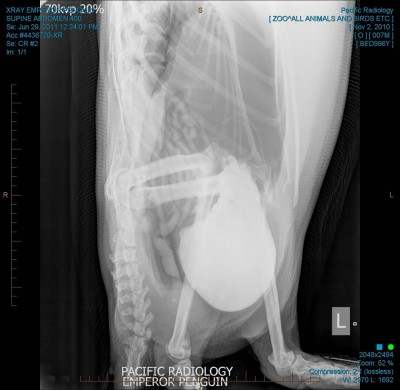

Il pinguino è ancora convalescente: due giorni fa è stato sottoposto a una endoscopia attraverso la quale sono stati rimossi dal suo stomaco e dalla gola i corpi estranei che aveva inghiottito scambiando per neve la sabbia della spiaggia su cui era approdato. La radiografia di questa mattina ha rassicurato l’equipe che l’ha curato: l’operazione ha avuto buon fine. Il consiglio ha stabilito che rimarrà in Nuova Zelanda, nello zoo di Welligton, fino a quando non sarà sufficientemente in salute e in forze per avere delle realistiche possibilità di sopravvivenza al viaggio.